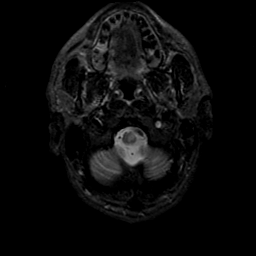

MR Study #21, November 3, 1991 -- Slice #3

[Home][Help][Clinical][Tour 1][Tour 2] Slice 3